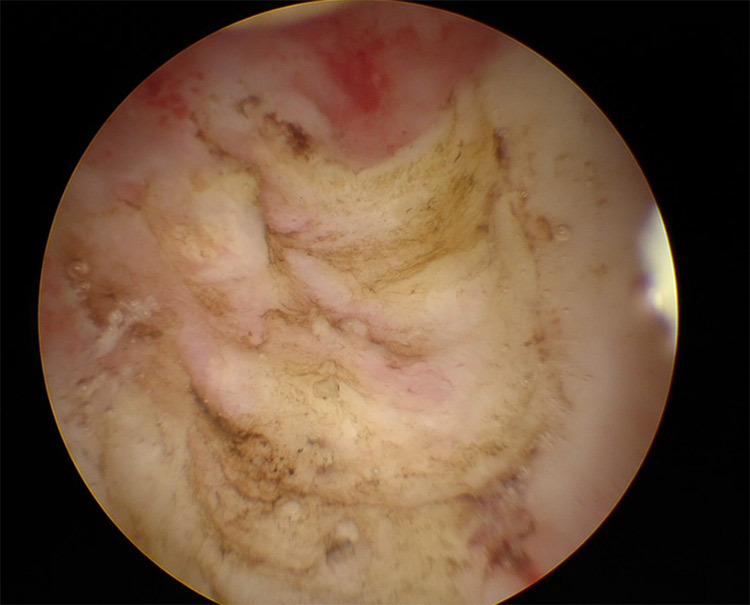

Οι παρακάτω τέσσερις εικόνες δείχνουν:

και οι δύο τελευταίες εικόνες κυστεοσκόπησης ( 3 και 4), δείχνουν πώς φαίνεται ο πολύποδας πριν την αφαίρεσή του και πώς φαίνεται το ενδομήτριο μετά την ολοκλήρωση της επέμβασης.

2. Χειρουργική αντιμετώπιση: Υστεροσκόπηση και Πολυπεκτομή

- Με μια ελάχιστα επεμβατική διαδικασία για την άμεση οπτικά εκτίμηση και αφαίρεση του πολύποδα χρησιμοποιώντας επεμβατική υστεροσκοπική τεχνική με ή χωρίς βιοψία ενδομητρίου.

Είναι η αφαίρεση υστεροσκοπικά ενός μικρού δείγματος ενδομητρικού ιστού για μικροσκοπική εξέταση όπως επίσης αν είναι δυνατόν αφαίρεση όλου του πολύποδα ή βιοψία από τον πολύποδα. Εξετάζεται αν υπάρχουν ανησυχίες για κακοήθεια βάσει ευρημάτων υπερηχογραφήματος ή παραγόντων κινδύνου της ασθενούς.